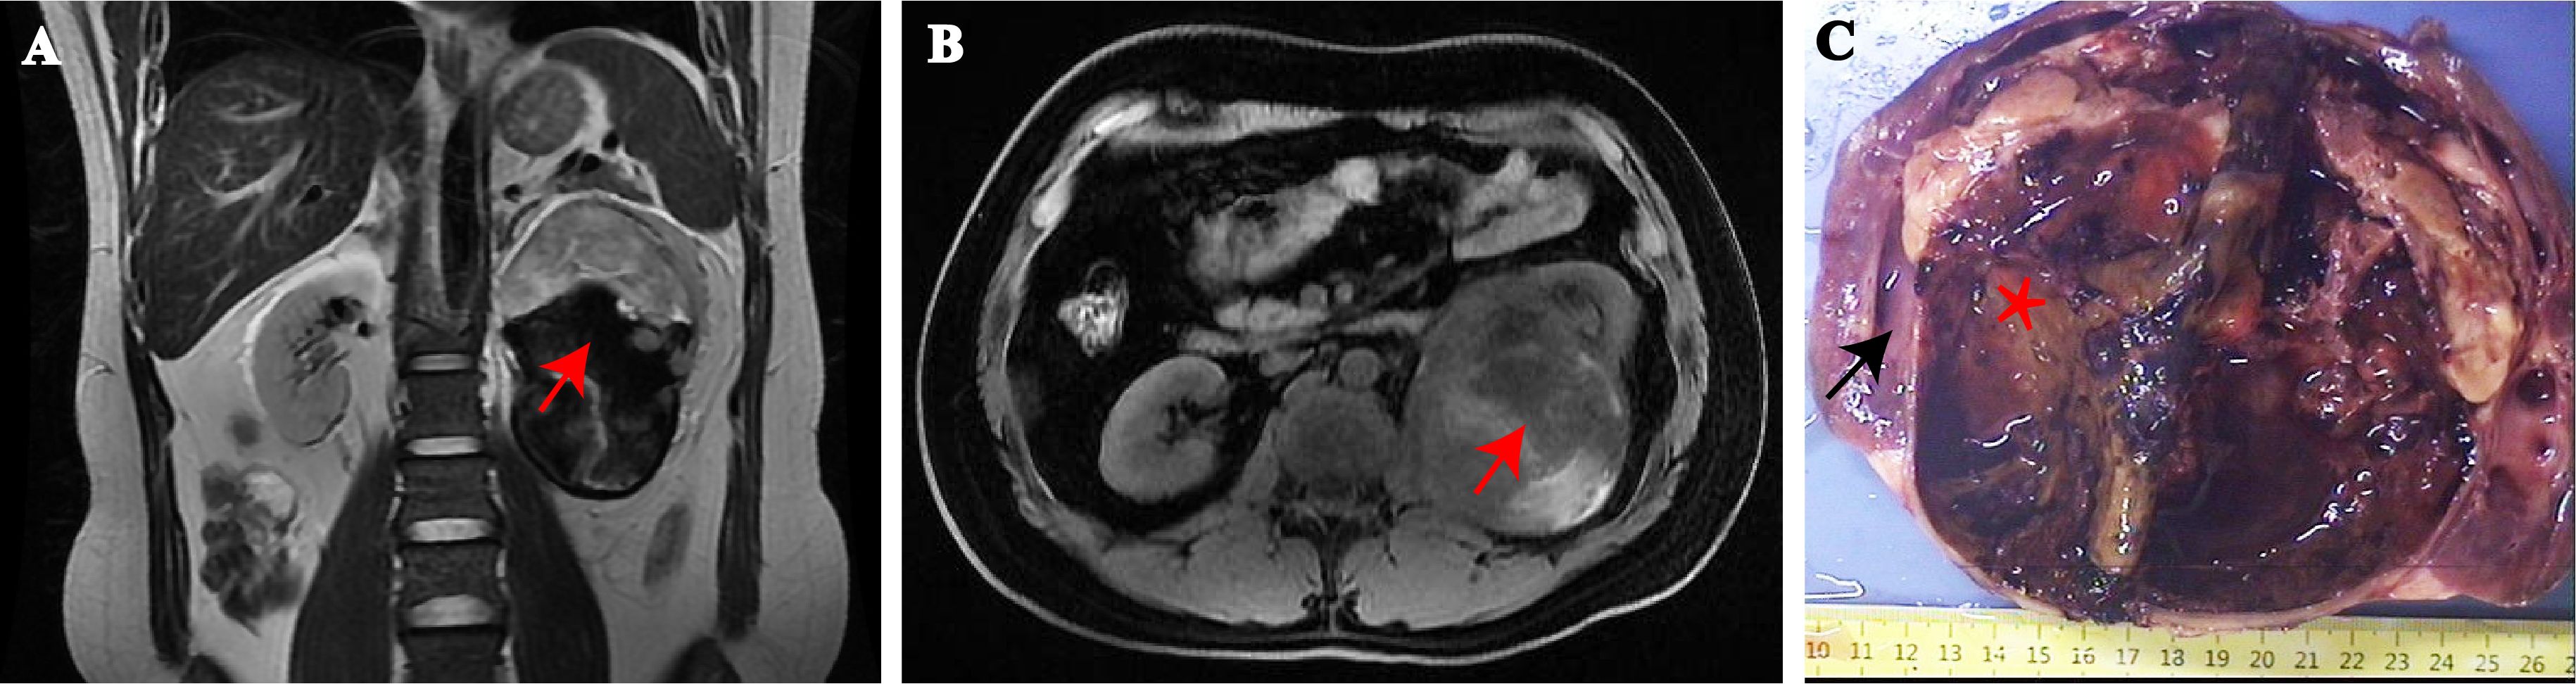

A 33-year-old overweight male patient (BMI, 25.9) presented with dull, constant left lumbar pain, accompanied by nausea, vomiting, and subsequent hematuria for 1 week. He had no family history of cancer or neurofibromatosis type 1. He did not smoke, drink, have irregular sleep habits, or frequent exposure to high temperatures and chemicals at work. Biochemical examination showed elevated low-density lipoprotein (LDL; 4.2 mmol/l). A large cystic-solid mass was found in the left kidney during a routine ultrasound examination. CT and MRI showed a large, encapsulated cystic-solid mass involving the left kidney, with gradual enhancement on post-contrast images, raising the possibility of renal cell carcinoma in differential diagnosis. The tumor measured ~13.4 × 9.8 × 7.8 cm, with relatively clear boundaries (Figures 1A, B). A left radical nephrectomy and lymph node dissection were performed.

MRI images A (coronal) and B (axial) show a renal mass indicated by red stars. Image C displays the gross specimen: black arrows point to renal tissue, while the tumor is marked by asterisk.

Figure 1. MRI showing a large tumor arising from the hilum of the left kidney. (A) Sagittal and (B) transverse view. (red arrows = tumor). Gross findings, the mass was located at the renal hilum and clearly demarcated from the surrounding renal tissue (C). (black arrows = renal tissue, asterisk = tumor).

Grossly, A protruding, round mass was found in the kidney, measuring approximately 13.0×10.0×8.0 cm at the renal hilum, sharply demarcated from the surrounding renal parenchyma, with a distinct fibrous pseudo-capsule. The cut surface of the mass exhibited a grayish-red color, a soft consistency, and a fish-flesh-like appearance. Additionally, areas of gelatinous, solid and hemorrhage areas were observed (Figure 1C). Microscopically, the tumor was composed of spindle tumor cells reminiscent of Schwann cells and large granular-like cells with eosinophilic cytoplasm. The granular-like cells were either distributed modularly or diffusely interspersed with the spindle cells (Figures 2A, B). The spindle tumor cells had minimal amphophilic cytoplasm and showed elongated, buckled or wavy nuclei with hyperchromatic or vesicular nuclei (Figure 2C). The granular-like cells were round-to-polygonal, with distinct cell borders and abundant, finely granular eosinophilic cytoplasm (Figure 2D). Nuclei varied in morphology, ranging from uniformly small and mildly hyperchromatic to larger and vesicular with distinct nucleoli. Mitoses, including atypical mitoses, were more easily found in granular-like cells compared with the spindle elements (Figure 2E). The normal renal tubules were frequently entrapped at the periphery (Figure 2F). The gelatinous areas are attributed to the presence of myxoid stroma, necrosis and hemorrhagic components within the tumor. Immunohistochemistry showed that both the spindle and granular-like tumor cells were positive for Nestin, Leu-7, PGP9.5, CD56 and BCL2 (Figures 3A–E). Tumor cells were negative for S-100 (Figure 3F), SOX10, Desmin, MyoD1, GFAP, keratin, EMA, WT1, CD34, STAT6, HMB45, Melan-A, P16, P53 and MDM2. Both tumor components showed complete loss of H3K27me3 staining, with retained expression in endothelial cells (Figure 3G). The entrapped renal tubules show positive staining for keratin7 and PAX8 (Figures 3H, I). The renal cell carcinoma was excluded due to spindle-shaped tumor cells and immunohistochemistry showed negative expression of keratin and EMA. A diagnosis of high-grade MPNST was confirmed, which was further classified as T2N0MX, stage IIIA.